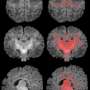

A study published in Environment International concludes that air pollution during pregnancy is associated with slower brain maturation in newborns. It is the first study to analyze brain development within the first month of life and stems from the collaboration between researchers at Hospital del Mar, the Barcelona Institute for Global Health (ISGlobal), and the CIBER area of Epidemiology and Public Health (CIBERESP).